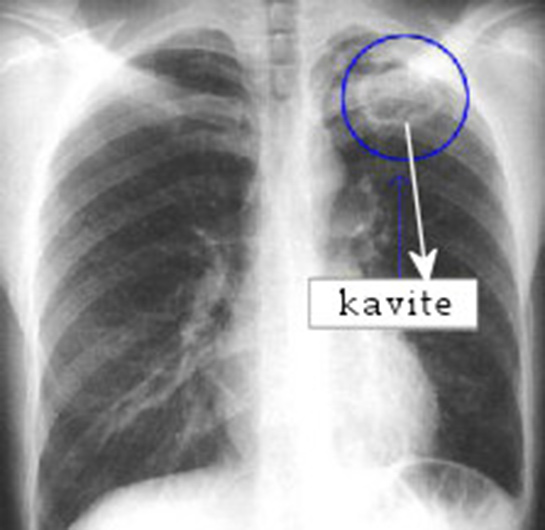

Dihye, öksürürken kan görmek ciddi bir durumun belirtisi olabilir. Bu, akciğerlerde veya solunum yollarında bir sorun olduğunu gösterebilir. Sigara kullanıcılarında bu durum daha da önemlidir çünkü sigara, akciğer kanseri, tüberküloz ve kronik obstrüktif akciğer hastalığı (KOAH) gibi ciddi hastalıklara yol açabilir. Basit bir enfeksiyon da kanlı öksürüğe neden olabilir, ancak kesin tanı koymak için bir doktora başvurman en doğru adım olacaktır. Doktor, gerekli tetkikleri yaparak durumu değerlendirecek ve uygun tedaviyi önerecektir. Lütfen, bu belirtileri göz ardı etmeyip en kısa zamanda bir sağlık profesyoneline danış.